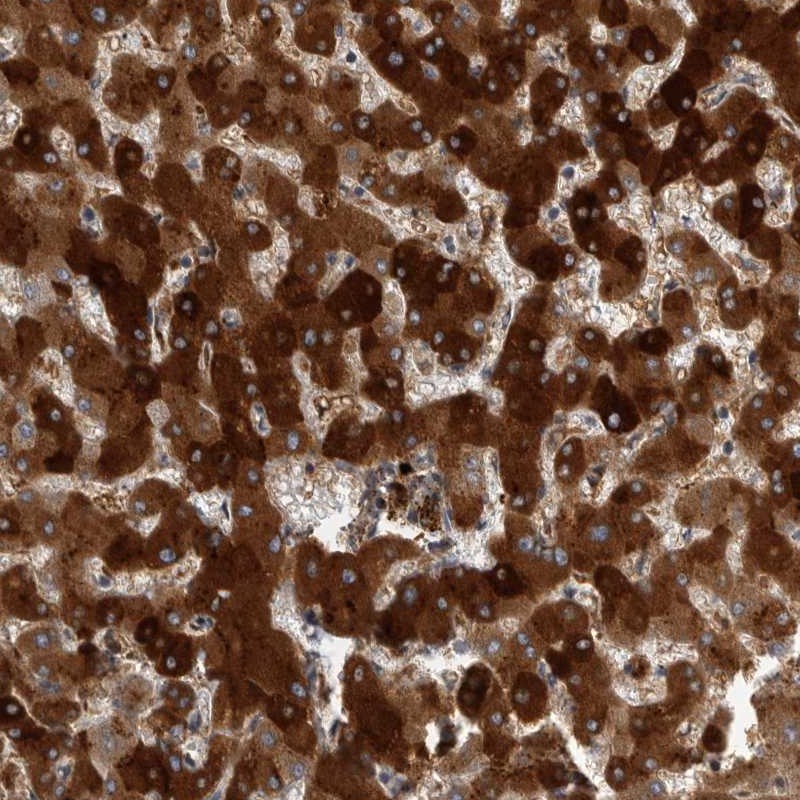

Immunohistochemical staining of human liver shows strong cytoplasmic positivity in hepatocytes.